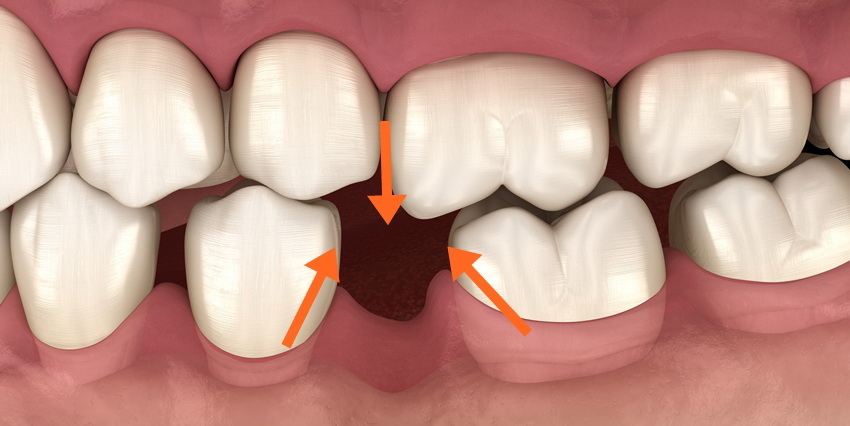

It is recommended that reconstruction is necessary, otherwise the adjacent teeth will tilt to the left and right, and the antagonistic teeth will extend toward the missing teeth.The back teeth cannot be seen, so why do they need reconstruction?To answer the above situation, why is reconstruction necessary if only the second molar is missing? Since the back teeth cannot be seen, why do we need to fill them? That is because the corresponding opposing teeth will extend towards the missing teeth, thus creating a height difference. If the teeth are not straight, there will be a blind spot for cleaning, which will almost always cause new caries on the adjacent teeth. . In addition, when the second molar extends toward the missing tooth, it is easy to cause the tooth root to be exposed, resulting in sensitivity and discomfort. Therefore, even if the back teeth are not visible, they still need to be treated in this situation to avoid subsequent problems.

In order to chew smoothly, teeth have the characteristic of being close to each other. Therefore, if the teeth are left unattended after extraction, the teeth on the opposite side will extend and grow towards the missing teeth area, and the adjacent teeth on the left and right will also gather towards the missing teeth area, causing irregular teeth. Condition.